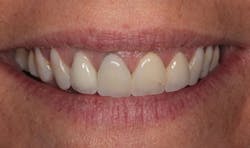

In Figure 1, you can see a close-up view of her smile as it was when she presented. She recently had noticed a fracture in both central incisor crowns and, since replacement was necessary, wanted to investigate the possibilities for improvement. The retracted facial view can be seen in Figure 2. Clinical and radiographic examination showed me that her overall dental health was good, with no periodontal disease or active caries. The patient expressed an interest in widening her smile and achieving a lighter color. The shade she desired was OM1 on the Vita Toothguide 3D-Master shade guide (figure 3).

Figure 2: Retracted facial view of the patient’s smile before treatment